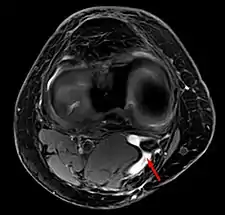

Diagnosis is by examination. A Baker's cyst is easier to see from behind with the patient standing with knees fully extended. It is most easily palpated (felt) with the knee partially flexed. Diagnosis is confirmed by ultrasonography, although if needed and there is no suspicion of a popliteal artery aneurysm then aspiration of synovial fluid from the cyst may be undertaken with care. An MRI image can reveal presence of a Baker's cyst.

Baker's cyst on axial MRI with communicating channel between the semimembranosus muscle and the medial head of the gastrocnemius muscle.